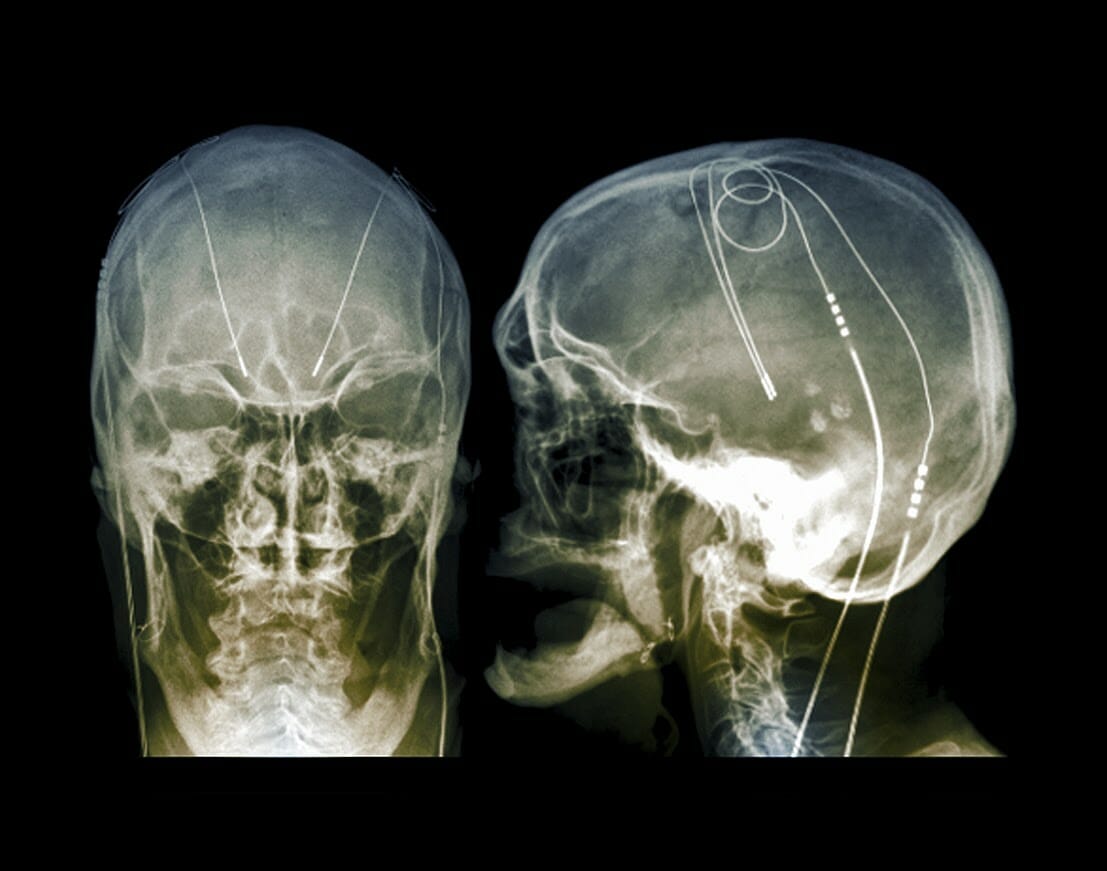

For patients with Parkinson disease, a postoperative home health-based care deep brain stimulation (DBS) model may be safe, effective, feasible, and capable of reducing travel burden for those who travel to receive DBS programming, according to study results published in JAMA Neurology.

A team of investigators conducted an open-label randomized clinical trial (ClinicalTrials.gov Identifier: NCT02474459) at University of Florida Health from 2017 to 2020 to assess the efficacy of home health DBS postoperative management in patients with Parkinson disease. They sought to improve therapy access and reduce travel burden.

Study researchers randomly assigned patients (1:1) to either receive standard of care or home health postoperative DBS management for 6 months following surgery. The home health postoperative management was conducted at home by a home health nurse who chose the DBS setting. Home health nurses did not have any previous experience providing DBS care and were aided by an iPad-based mobile application for the Parkinson disease DBS system.